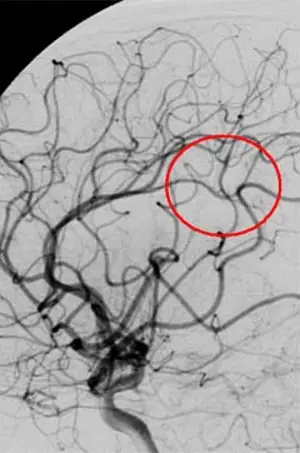

По имеющимся МРТ и КТ снимкам компьютер строит трехмерную модель опухоли простаты и выделяет красным зону высокого облучения

Поскольку этот метод назвали хирургией, то аппараты, используемые для лечения, называют «ножами». Это источники излучения. Кибер-нож — подвижная установка, поэтому ее можно использовать для лечения рака любого органа.

- Моделирование. Через неделю после маркировки врач делает КТ- и МРТ-снимки. Это нужно для уточнения размеров и положения опухоли. После этого медицинская команда, уже без вашего участия, проводит расчеты и создает компьютерную симуляцию. Так рассчитывается наилучшее положение тела и линейного ускорителя.

- Планирование. Используя полученные КТ- и МРТ-снимки лечащая бригада рассчитывает дозу и напраления излучения.